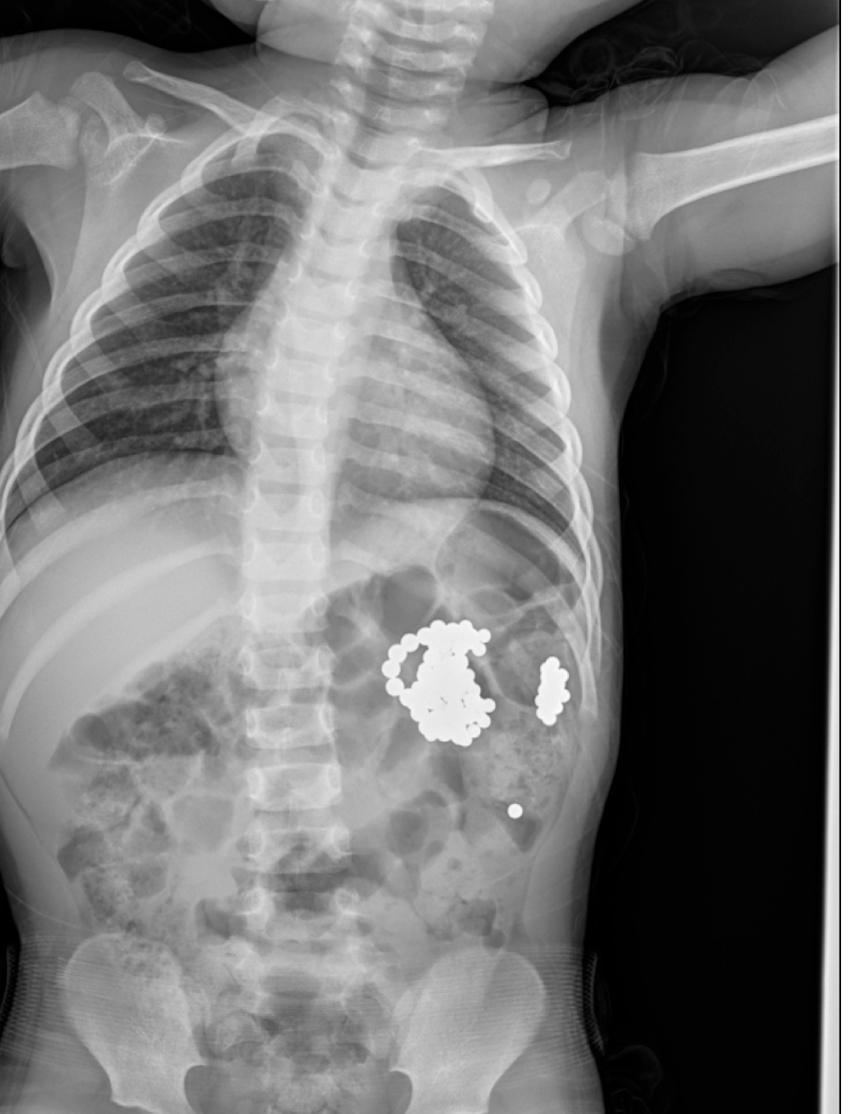

Kecepatan tangan toddler memang mengalahkan kecepatan cahaya. Jadi untuk teman-teman para orang tua yang memiliki balita. Ayo jangan lupa singkirkan benda-benda kecil di sekitarnya. Bagaimanapun wujudnya dan bentuknya. Magnet, plastik, atau apapun. Pada kasus ini akhirnya harus tindakan endoskopi lambung, ditemukan 30 magnet kecil berkelompok menekan dinding lambung, lalu diangkat dengan Roth net dalam dua kali pengambilan.